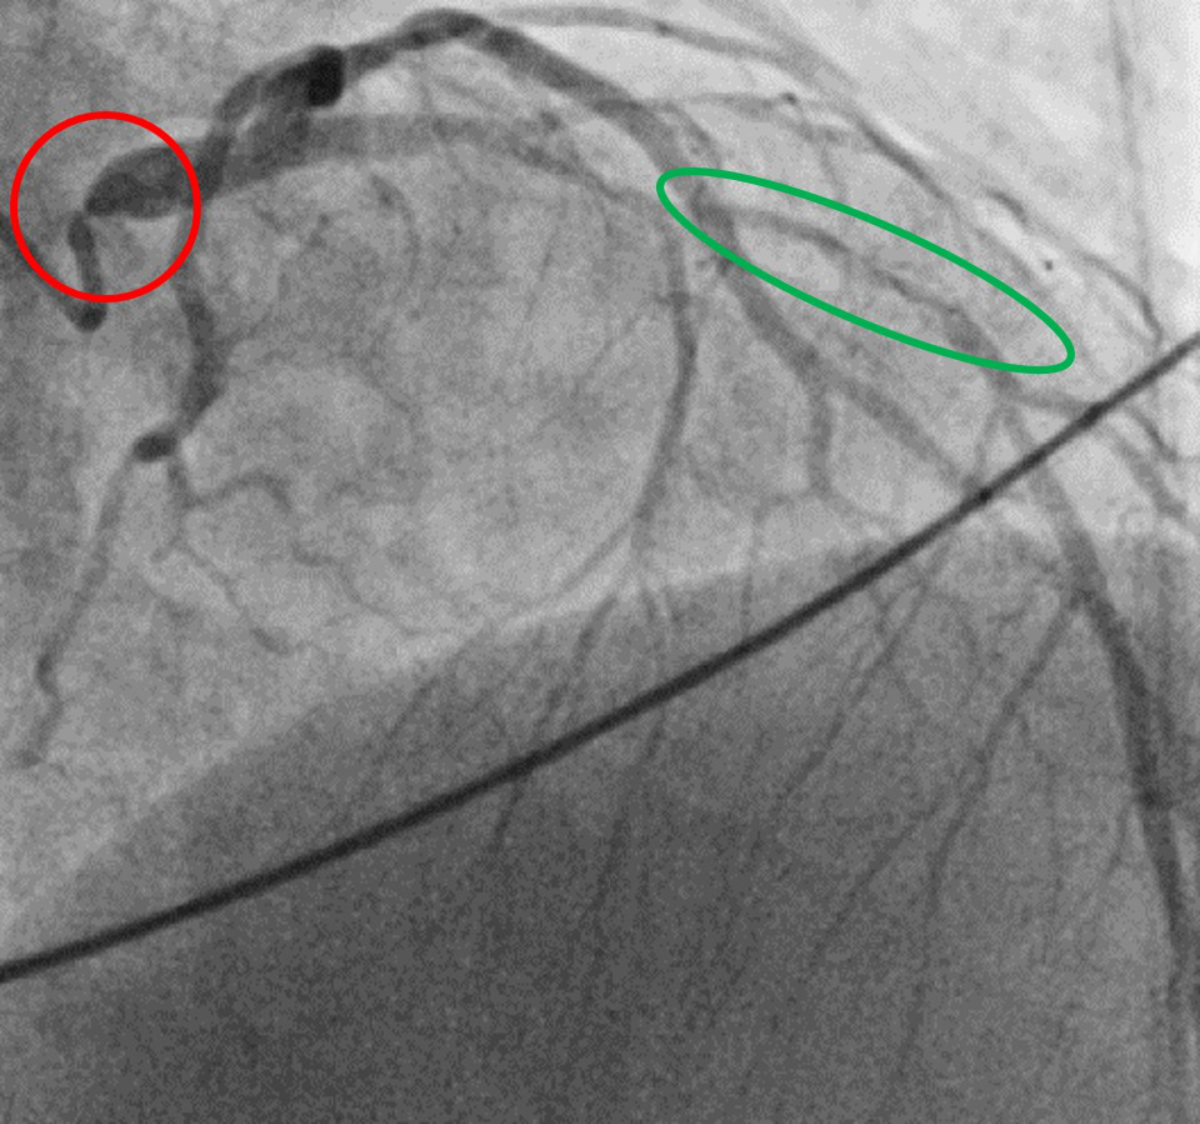

A 42-year-old man with homozygous familial hypercholesterolaemia and a confirmed homozygous LDLR mutation experienced significant progression of his atherosclerotic cardiovascular disease over the years, despite receiving maximum lipid-lowering therapy. At the age of 11 years, he underwent his first percutaneous coronary intervention (PCI) for a high-grade stenosis of the left main coronary artery. Since then, he has been treated with high-intensity statins, ezetimibe and weekly apheresis. In 2021, aged 39, he underwent triple coronary bypass surgery and replacement of the ascending aorta because of progressive coronary artery disease (figure 1) and a highly calcified aortic root. Two years later, in 2023, he experienced a myocardial infarction caused by an acute occlusion of the right coronary artery (saphenous vein graft chronically occluded). Simultaneously, a computed tomography angiography scan demonstrated diffuse peripheral arterial occlusive disease with atheromatous infiltration in the ilio-femoral region (figure 2) as well as bilateral atheromatous infiltration of the carotids, indicating systemic polyvascular atherosclerotic infiltration.

Figure 1Coronary angiogram. Diagnostic coronary angiogram showing an ostial subtotal left main stenosis (red circle) as well as significant stenosis in the mid left anterior descending artery (green circle) before coronary artery bypass surgery in 2021 (age 39 years).